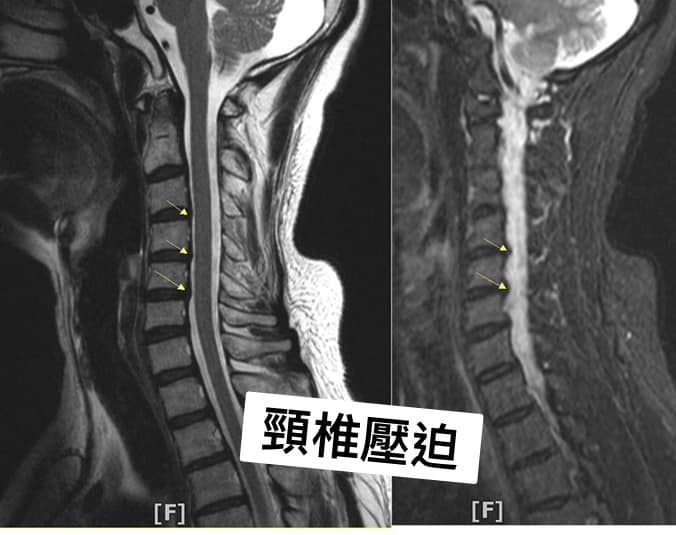

Cervical Spine Treatment Cases 頸椎治療案例 #特殊案例頸椎手術後又再度突出案例 #感謝台中劉大哥熱情見證 #親自手捏醫師娃娃公仔... 2020.11.18 #頸椎病居然會導致手快速萎縮 #脊髓型頸椎病案例 #感謝高雄王大哥熱情見證 #頸椎整合... 2020.11.13 #神經根型頸椎病讓人痛到無法入眠 #感謝新店陳小姐熱情見證 #患者的疼痛日誌讓人感動 ... 2020.11.11 #左邊膏肓長期刺痛案例原來是頸椎病 #之前一直當作肩關節問題處理沒效 #高濃度葡萄糖... 2020.11.03 #腰椎整合醫案逆轉勝 #曾經大痛到無法走路 #坐骨神經痛就是那們痛 #感謝桃園蘆竹張小... 2020.10.29 #特殊案例之味覺錯亂 #原本香甜奶油車輪餅患者覺得酸臭 #按照頸椎病治療五次後突然味... 2020.10.27 頸椎病產生的嚴重交感神經症狀 治療前後比對 2020.10.23 #等待快一年的頸椎受傷醫案追蹤 #頸椎脊髓損傷導致左邊手麻合併下肢無力患者 #前後一... 2020.10.14 #最複雜多變最痛苦難受的頸椎病 #多年的胸悶與心悸伴隨呼吸困難 #交感神經型頸椎病 #... 2020.10.13 #頸椎曲線弧度非常重要 #頸椎弧度有可能逆轉嗎 #短短三個月時間看到效果 #患者超認真... 2020.10.09 #打壘球居然腳不聽使喚跑不起來 #更恐怖的是勉強跑起來還無法剎車 #洗頭往後仰身體背... 2020.10.07 #疼痛三年頸椎病患者親手寫下治療紀錄 #交感神經型頸椎病 #症狀錯綜複雜 2020.10.02 #困擾四年多胸悶手麻頭暈醫案 #一切原因居然是頸椎出問題 #交感神經型頸椎病症狀錯綜... 2020.09.11 #交感神經型頸椎病引起的耳鳴 #耳鳴將近八個月終於得到重大改善 #曾經耳鳴到無法睡覺... 2020.08.22 #感謝板橋蘇先生熱情見證 #神經根型頸椎病卡壓 #曾痛痛到左手無法騎單車撥桿 #麻脹刺... 2020.08.04 ← 上一頁 4 5 6 7 8 下一頁 →